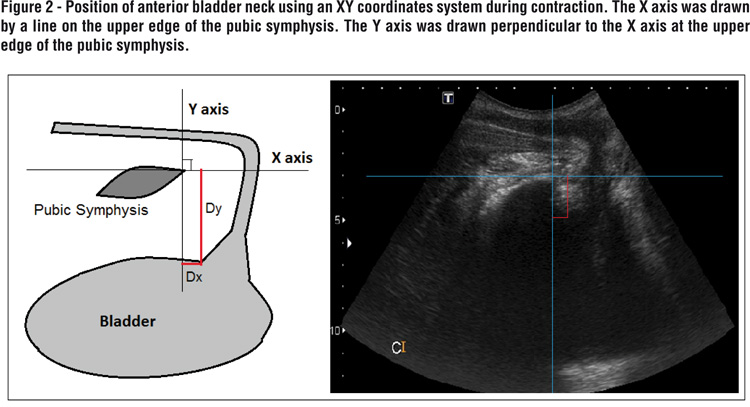

The position of the bladder neck was determined at rest, during the Valsalva maneuver and during pelvic floor contraction. Measurements were made using an XY coordinate system, with the pubis as the reference point. The X axis was drawn by a line on the upper edge of the pubic symphysis. The Y axis was drawn perpendicular to the X axis at the upper edge of the pubic symphysis.

For exact positioning of the bladder neck, we used the most proximal urethral wall, in the immediacy of the bladder. We calculated the anterior and the posterior bladder neck mobility under conditions of rest, pelvic floor contraction and Valsalva maneuver. The movement of the bladder neck was calculated by the following formula: √(x2-x1)²+(y1-y2)², where x1 and y1 represent the rest coordinates (8,9,16-19) (Figure 2).